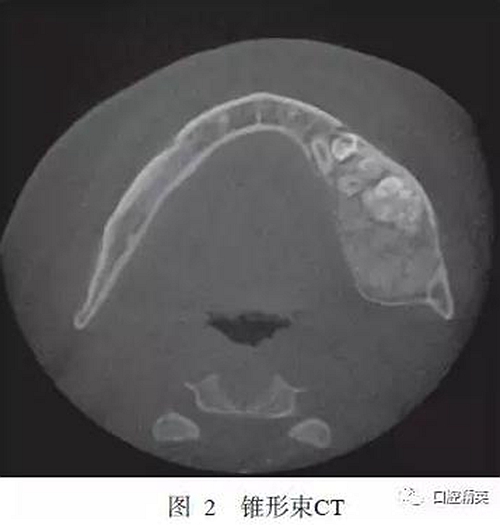

錐形束CT示:左下頜D5~D7缺失,D5~D7位置下頜骨內(nèi)可見牙瘤樣結(jié)構(gòu),左下頜骨膨隆明顯,膨隆向上至下頜骨升支乙狀切跡下方,向下至下頜骨下緣,向前至下頜骨體D5位置,向后至下頜升支中份,骨質(zhì)膨隆內(nèi)可見鈣化程度不同的阻射影(圖2)。